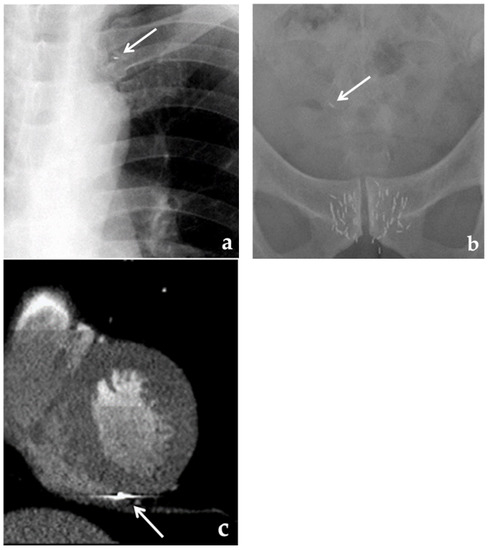

- Sugawara, A.; Nakashima, J.; Kunieda, E.; Nagata, H.; Mizuno, R.; Seki, S.; Shiraishi, Y.; Kouta, R.; Oya, M.; Shigematsu, N. Incidence of seed migration to the chest, abdomen, and pelvis after transperineal interstitial prostate brachytherapy with loose (125)I seeds. Radiat. Oncol. 2011, 6, 130. [Google Scholar] [CrossRef] [PubMed]